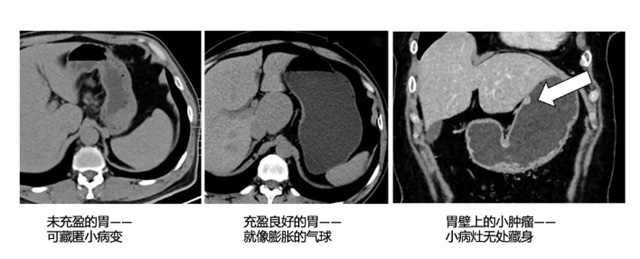

然而CT的檢查跟X射線不一樣,X光線是扁平化的,CT就像切片那樣,切片內部細節一目了然。人體組織結構重疊的部分變少。圖像分辨率更高更清晰。可以觀察細小的病變。特別是腹部做CT檢查時候,幾小時禁食檢查前充分喝水,提高疾病的檢出率。